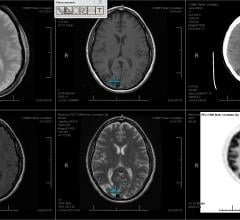

There are no laboratory tests to diagnose migraines, depression, bipolar disorder and many other ailments of the brain. Doctors typically gauge such illnesses based on self-reported symptoms and behavior. Now, a new study shows that a kind of brain scan called functional connectivity magnetic resonance imaging (fcMRI), which shows how brain regions interact, can reliably detect fundamental differences in how individual brains are wired. As such, the technique potentially could be used to distinguish healthy people from people with brain diseases or disorders, and provide insight into variations in cognitive ability and personality traits.